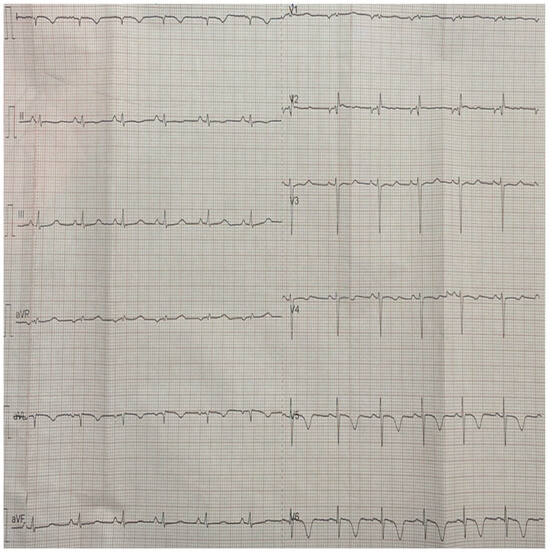

2. Case Report